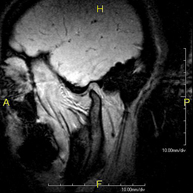

RM ATM (Articulació temporo-mandibular)Prova diagnòstica no invasiva que consisteix en l'obtenció d'imatges d'alta definició anatòmica de les articulacions temporo-mandibulars mitjançant l'ús d'un camp electromagnètic i ones de ràdio (amb un emissor i un receptor). No utilitza radiació ionitzant. Es realitza un estudi funcional de les ATM, en les diferents fases d'obertura i tancament de la boca. Indicacions: dolor, bloqueig de l'articulació i sorolls en mastegar.